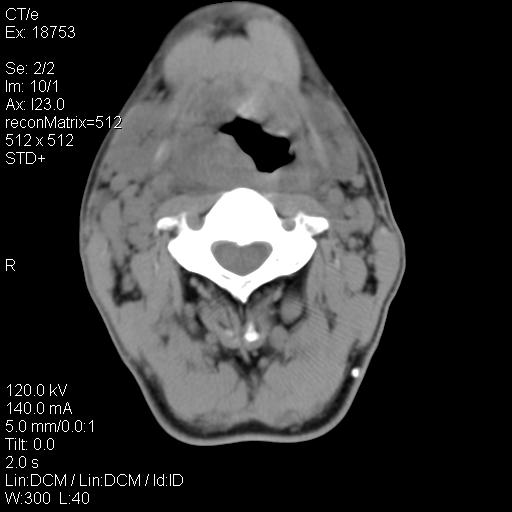

标题: CT21693:男 58岁 右侧咽部疼她2天余 PE:右侧扁桃体肿大 压痛 [打印本页]

标题: CT21693:男 58岁 右侧咽部疼她2天余 PE:右侧扁桃体肿大 压痛

喉部新生物,喉癌可能大,建议喉镜取组织活检。

考虑感染性病变可能性大,建议抗炎治疗后复查,必要时鼻咽腔镜活检排除占位。

结合病史,考虑感染性病变;建议抗炎治疗复查排除肿瘤性病变。

右化脓性扁桃体炎症伴咽后壁脓肿形成.

以下是引用zjzjr在2009-8-19 21:07:00的发言:[br]右化脓性扁桃体炎症伴咽后壁脓肿形成.